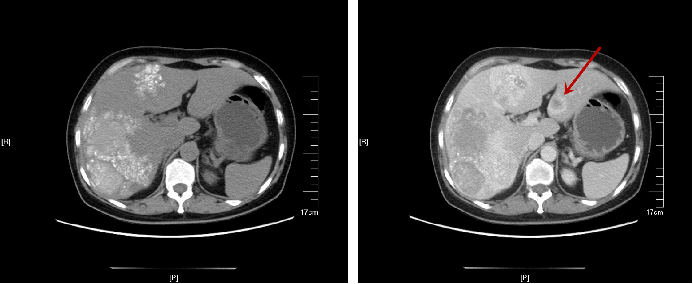

患者左肝为转移病灶,但右肝病灶性质无法明确,进一步行PET-CT检查:

①结肠肝曲肠壁明显增厚,FDG代谢增高,转移可能大;肠周数枚小结节,FDG代谢目前未见明显增高;肝左叶外侧段局灶性FDG代谢增高,MT不除外。

②肝脏明显增大,两叶广泛颗粒样钙化伴局部囊性密度影,考虑肝棘球蚴病可能。

至中国疾病预防控制中心寄生虫病预防控制所查血清检验抗体均为阴性。

至我院MDT,考虑为左右肝多发广泛转移,属不可切除肝转移患者,治疗以姑息化疗为主,如经济条件允许联合靶向治疗。

△治疗前